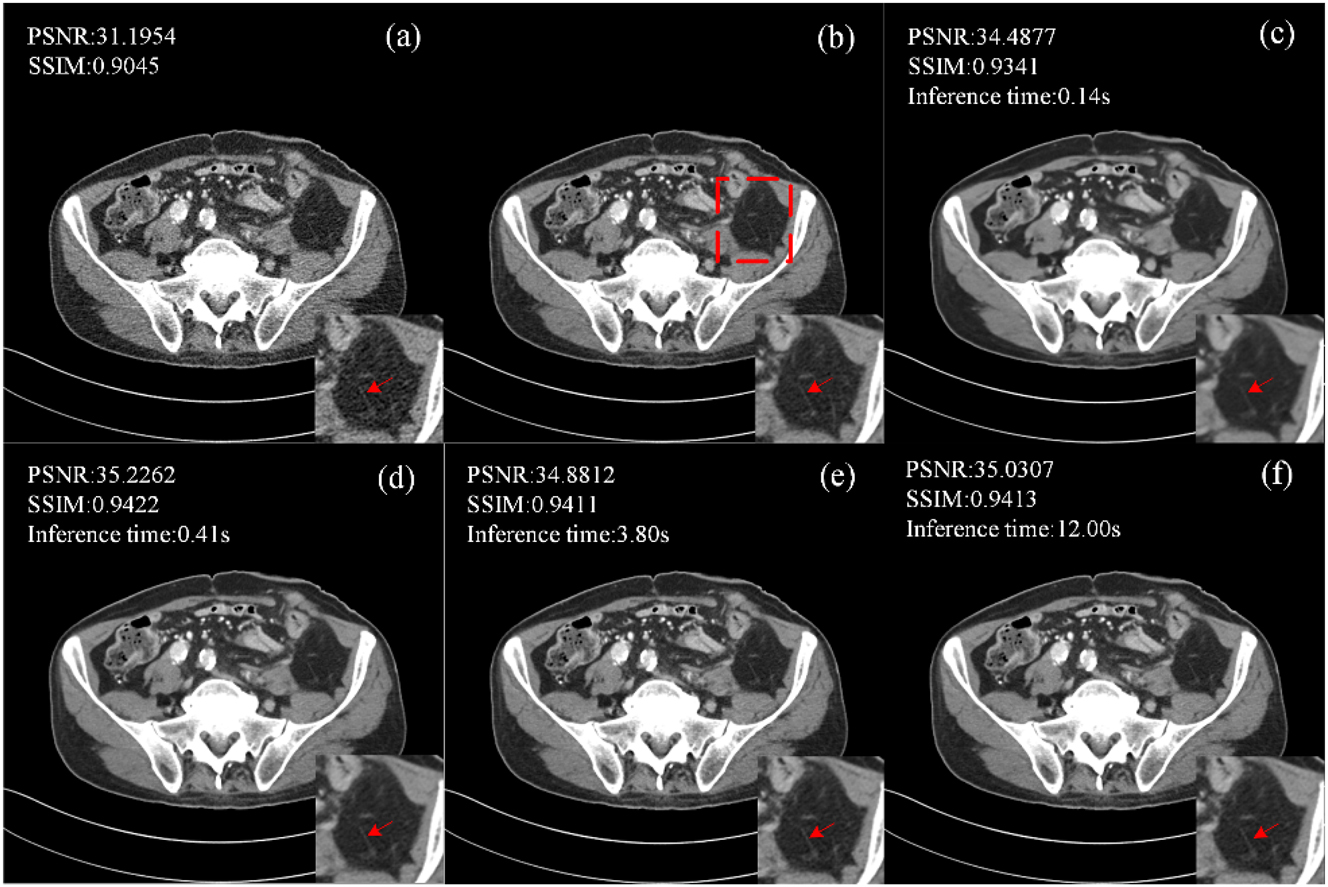

The performance of CECDM in training and inference was evaluated at T=1, 10, 50 and 200. Figure 6 shows the images after noise reduction with different T values. When T=1, CECDM is a one-step restoration, the edge of the image after noise removal is blurred, and the texture details are not clear. With the increase of T, the organizational boundary becomes clearer. At T=200, the degree of detail retention of the image is better than that of the image at T=50, but the inference time also increases significantly.

Ablation studies of CECDM with different T settings (a) LDCT, (b) NDCT, (c) T=1, (d) T=10, (e) T=50, (f) T=200.

When T=10, the PSNR and SSIM values of CECDM are the highest, and the image after noise removal is the closest to NDCT visually. When T≥50, the quantitative performance of CECDM decreased gradually. When T=200, PSNR increases to a certain extent. Therefore, considering the sharpness of the denoised image, quantitative performance, and inference time of the method, T=10 is a suitable setting for CECDM.